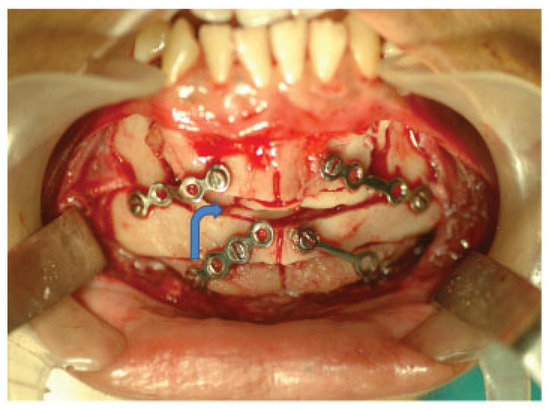

A Modified Kole's Osteotomy for Correction of Anterior Open Bite and Macrogenia in a Cleft Patient

:Surgical Method